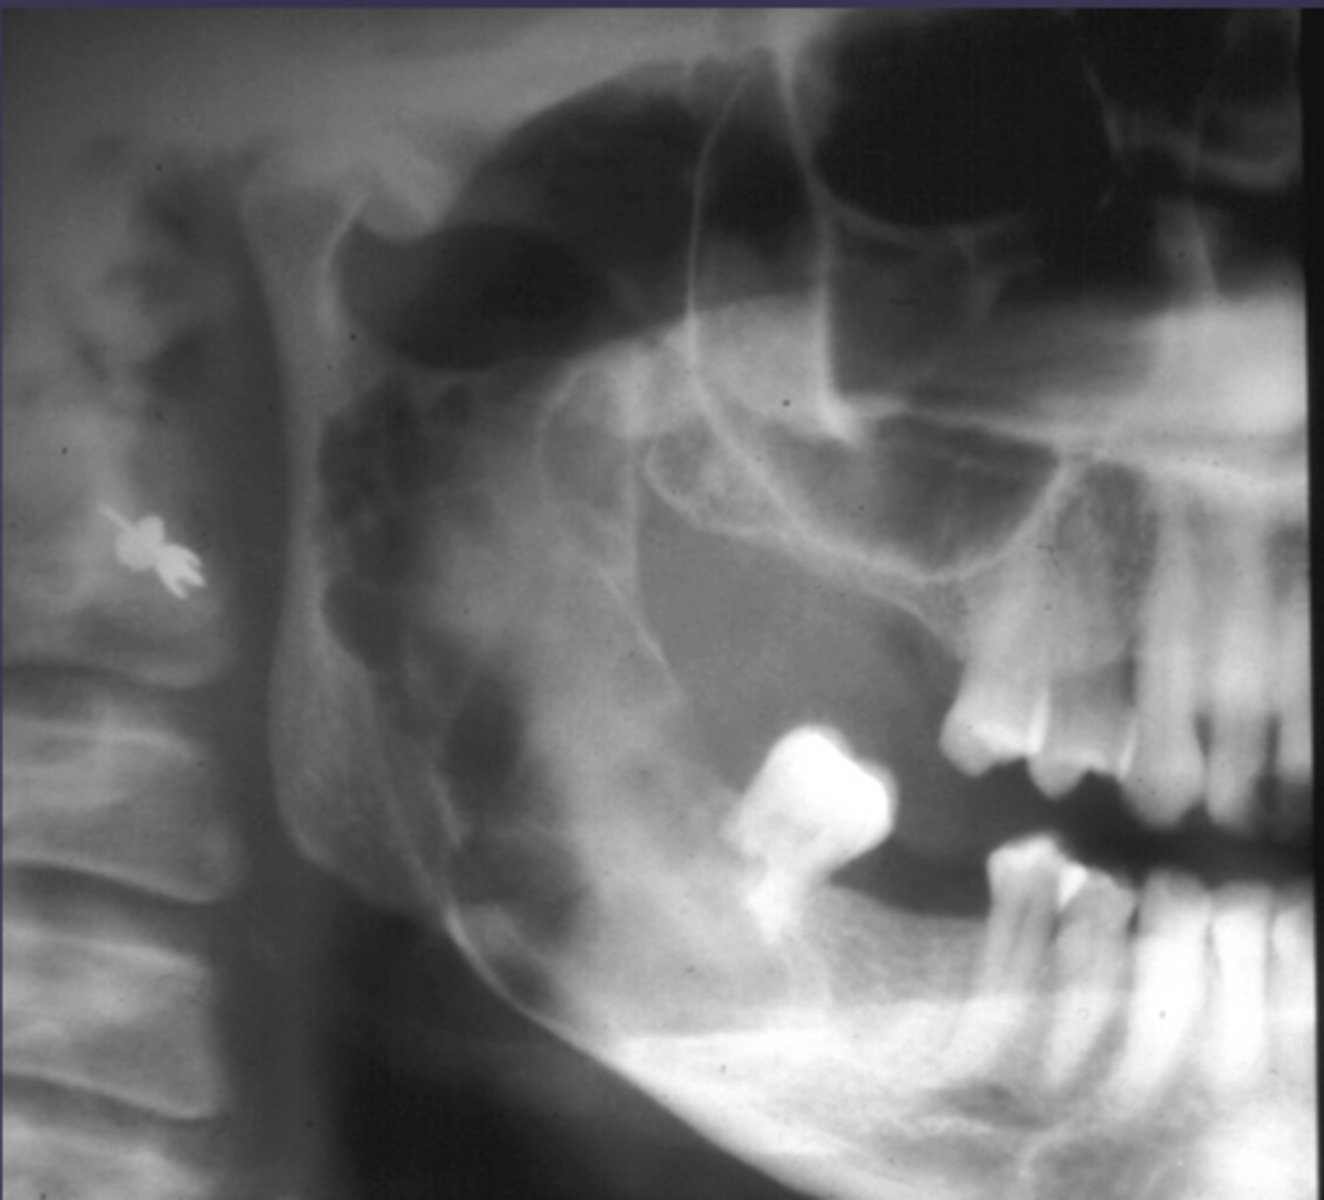

How would you describe the lesion?

- Ill-defined moth eaten area in the posterior mandible

- Radiopacities extending beyond the mandibular borders.

what category would you put this lesion into?

malignant

What would be a differential diagnosis for this lesion?

- Osteogenic sarcoma

- Squamous cell CA